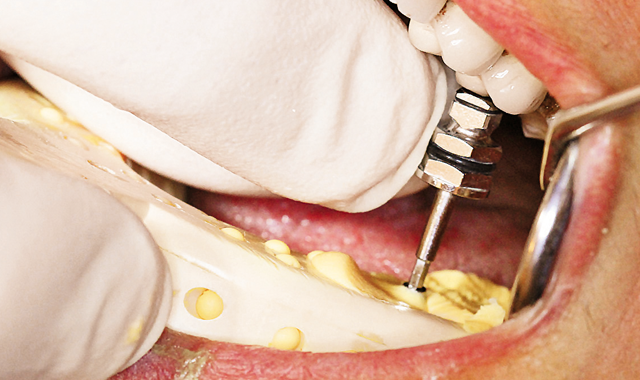

Fig. 13 Placing abutment.

A screw-retained direct zirconia crown was fabricated and placed (Fig. 13, above; Figs 14-16, below).

Fig. 14 Abutment for screw-retained crown.